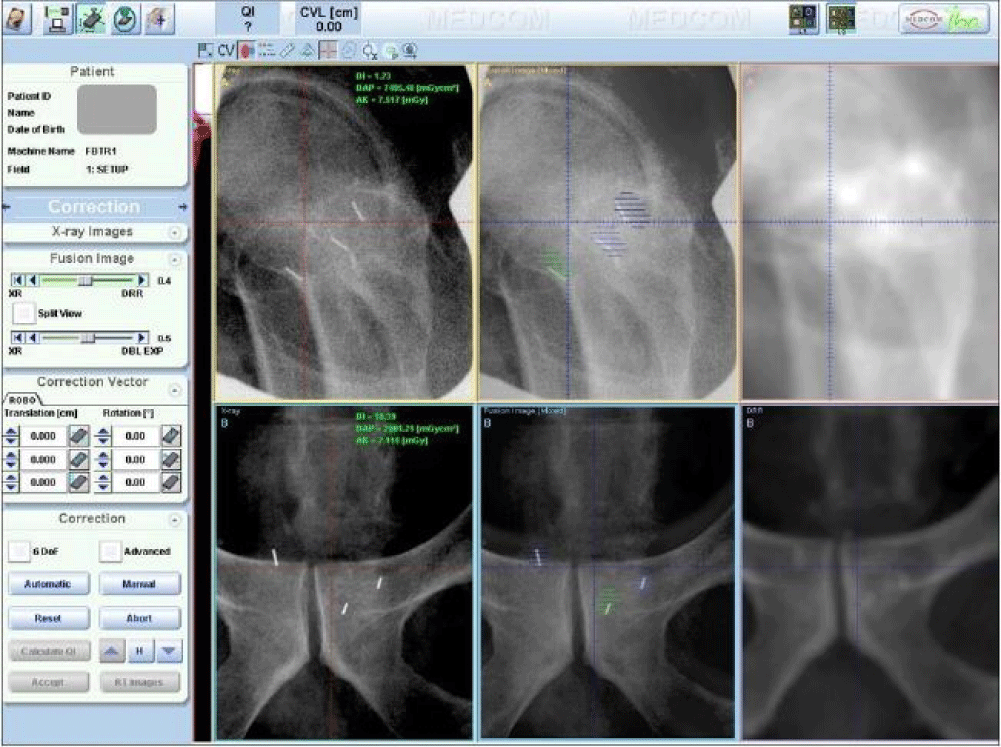

Six cases of various disease sites, including brain, head & neck (parotid), lung, prostate, pelvis, and bladder, were used in this study. For each case, the planning CT images and a pair of portal orthogonal x-ray images were loaded into the VeriSuite system. The planning CT images were obtained using a GE Lightspeed RT16 CT scanner (GE Healthcare, Waukesha, WI), with a slice thickness of 1.25 mm for brain, parotid, and prostate cases, and 2.5 mm for the other cases. The orthogonal x-ray image pair was captured during patient setup at a random fraction before a correction shift was applied and inspected by a physicist to ensure the portal images were typical for the patient. 10 radiation therapists (RTs) were selected as observers. For all six cases, each RT reviewed the same set of x-ray and DRR images and manually registered them case by case. Bony anatomy within the region of interest was used for brain, head & neck, lung, pelvis, and bladder cases. For the brain case, in addition to the manual alignment performed by the 10 RTs, we tested the automatic registration method and compared to the manual registration. For the prostate case, three VisiCoil fiducial markers of 0.5 mm in diameter x 5 mm in length (IBA Dosimetry, Bartlett, TN, USA) were implanted in the prostate. Each fiducial marker was contoured and expanded by 1 mm for use in portal image registration. Three image alignment methods were tested for the prostate case: 1) fiduical marker alignment- matching fiducial markers on the x-ray image to the expanded contours on the DRR, 2) bony anatomy alignment- matching bony anatomy between x-ray and DRR, and 3) hybrid alignment- matching bony anatomy for rotational correction and fiducial markers for translational correction. Figure 1 shows a screen shot of the image registration with VeriSuite using fiducial marker alignment for a prostate case.

Figure 1: A screenshot of the VeriSuite interface showing a prostate case registration using fiducial marker alignment. Top three images are lateral view and the bottom three images are posterior-anterior view. Left are digital x-ray images, right are DRRs, and middle are fusion images.